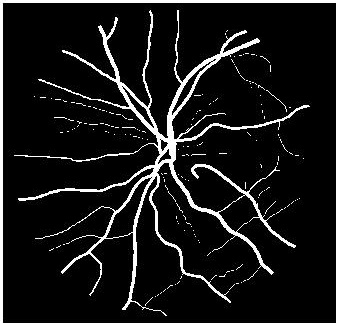

Figure 4 (a) shows an example retinal image followed by its ground truth manual segmentation in Figure 4 (b). Figure 4 (c) shows segmentation result for scaling factor when using the original HR images to train the U-Net followed by the results when trained on the super resolved images generated by , (Figure 4 (d)), (Figure 4 (e)), (Figure 4 (f)), SR-RF (Figure 4 (g)), SSR (Figure 4 (h)) and (Figure 4 (i)). Obviously the results from provide results most similar to those of HR images. This is also validated by the quantitative results in Table 3. The areas where different methods are unable to obtain accurate segmentation are highlighted by yellow arrows. Due to poor quality of super resolved images most of the methods do not segment the finer vasculature structures, while SSR and SR-RF are unable to segment some of the major arteries. Importantly, our method performs much better than the low resolution image () which performs poorly due to low resolution.

![]() |

| (a) | (b) | (c) | (d) | (e) |

| (f) | (g) | (h) | (i) | (j) |